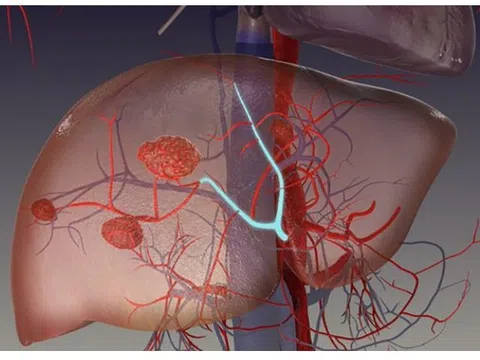

Đau tức hạ sườn, ăn kém, sút cân… là dấu hiệu bệnh gì?

U máu gan là dị dạng mạch máu bẩm sinh và là khối u lành tính hay gặp nhất ở gan. Nhiều người nhập...